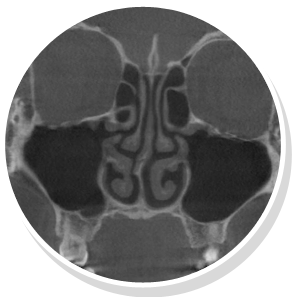

낮은코 내부구조 CT 사진 비중격 만곡증

낮은코 내부구조 CT 사진 커져있는 코덧살(비염)

비중격만곡증 교정술, 고주파 비염수술로 코의 기능을 회복시킴

절골술 및 비중격만곡증 교정술로 휘어진 코 교정